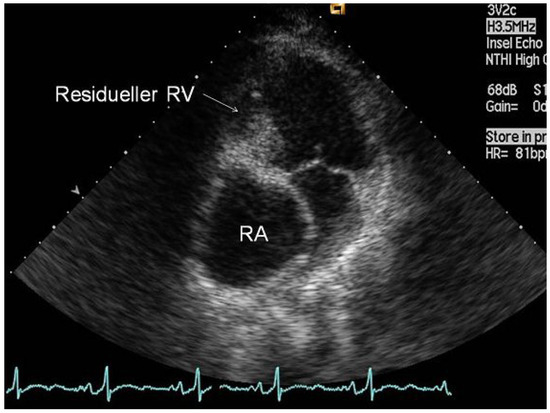

Die Fontan-Konversion—Oder das Schicksal, Die Erste zu Sein

We report the case of the first patient with tricuspid atresia in whom an “old-fashioned” Fontan operation with an atriopulmonary anastomosis was performed in our hospital 18 years ago. Complications of the former “classical” Fontan circulation can include progressive right atrial dilatation leading [...] Read more.

We report the case of the first patient with tricuspid atresia in whom an “old-fashioned” Fontan operation with an atriopulmonary anastomosis was performed in our hospital 18 years ago. Complications of the former “classical” Fontan circulation can include progressive right atrial dilatation leading to tachyarrhythmias, flow energy loss, obstruction of pulmonary veins, right atrial thrombi and the formation of pulmonary arteriovenous fistulas. In order to palliate our patient from recurrent atrial tachyarrhythmias and increasing haemodynamic disturbances, the previous “old-fashioned” Fontan circulation was surgically revised and converted according to a “modern” type of extracardiac Fontan circulation with additional anti-arrhythmic procedures. The post-operative course was uneventful. After recovery from surgery, the patient’s quality of life improved. She is free from atrial tachycardias and shows an increased exercise capacity. We will briefly discuss the complications of the classical Fontan circulation and the possible risks of the Fontan conversion. After having been the first Fontan patient in our center, our patient was again the first to require a major revision of its circulation. Full article